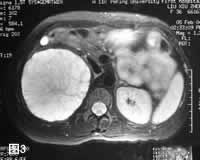

CT:平扫示右肾上极低密度类圆形占位,CT值30~35HU,边缘光滑(图1)。增强扫描可见肿瘤呈多房状,间隔强化明显,外缘及腔内未见强化(图2)。